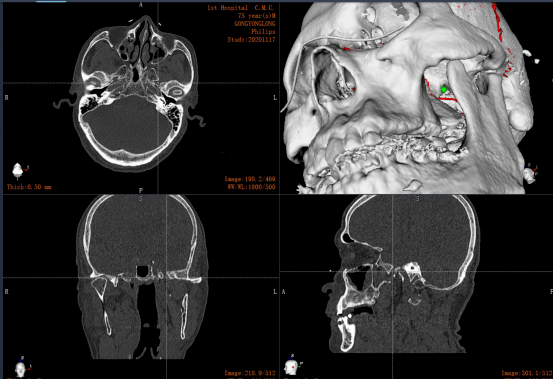

医·术|中国医大一院首次完成机器人辅助三叉神经痛手术

图片尺寸553x380